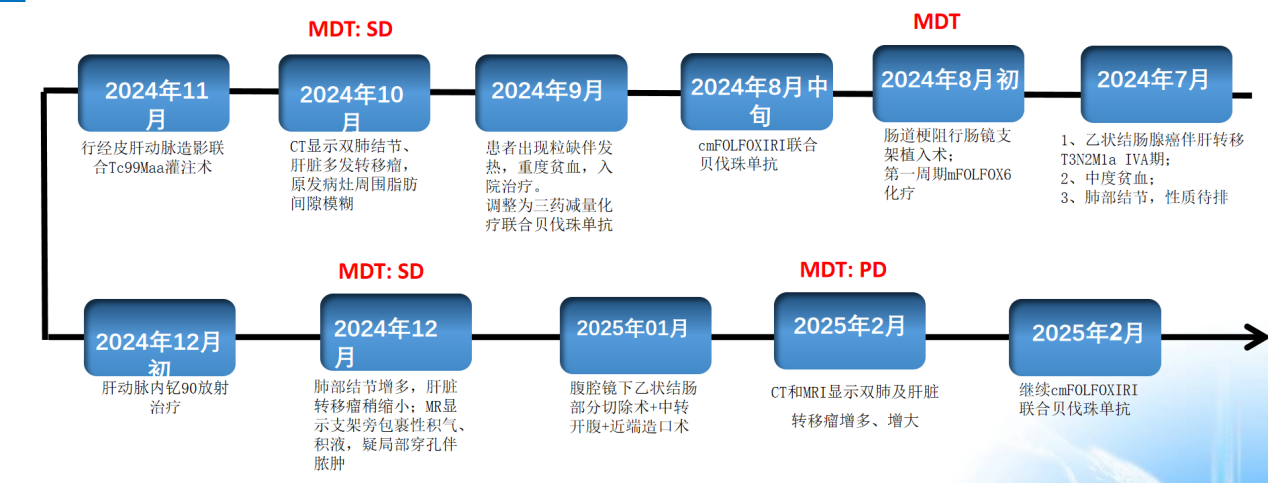

编者按:在晚期结直肠癌肝转移(CRLM)的诊疗中,多学科协作(MDT)模式已成为延长生存、改善生活质量的核心策略。本期《岂有此“例”》所报道的病例来自重庆医科大学附属第一医院结直肠癌MDT团队,由朱婧教授在2025 POST-ASCO GI大会上进行了报告。该病例患者为45岁乙状结肠癌伴肝转移男性,历经三药化疗联合靶向、钇90选择性内放射治疗(SIRT)、外科手术干预等多重治疗波折,在肿瘤进展与并发症中博弈。该案例不仅展现了基因检测指导下的精准治疗决策,更揭示了局部治疗与全身治疗协同的潜在价值,为晚期CRLM的临床实践提供了极具参考意义的范本。

二、治疗历程:MDT驱动下的动态决策

2024年8月5日:第一次MDT

初步诊断:乙状结肠腺癌伴肝转移(cT3N2M1a IVA期);中度贫血;肺部结节,性质待排。

治疗实施

鉴于基因检测结果和患者姑息治疗目标,转至肿瘤科接受FOLFOXIRI联合贝伐珠单抗化疗方案。

2024年8月24日,患者接受了第一周期cmFOLFOXIRI(奥沙利铂+ 伊立替康+5FU/亚叶酸钙)联合贝伐珠单抗的三药治疗。

考虑患者重度贫血,既往三药化疗患者出现粒缺伴发热,化疗耐受性差,遂于2024年9月10日予以患者三药减量化疗,考虑患者获益比,继续使用贝伐珠单抗。同时,采用长效升白针来预防和治疗粒缺。2024年9月10日至10月24日,予以患者cmFOLFOXIRI+贝伐治疗4周期。

治疗4周期后,肝脏转移灶较基线缩小约20%(图5/6),CEA从532.4 ng/ml降至217.3 ng/ml,CA199从344.2 U/ml降至172.9 U/ml,评估为SD。

2024年11月4日,第二次MDT

下一步治疗方案:鉴于肝脏转移灶仍显著,MDT团队考虑联合钇90放射治疗(SIRT)以增强局部控制

2024年11月8日~22日行cmFOLFOXIRI治疗2周期,停用贝伐珠单抗,为后续治疗准备。

2024年12月3日行肝动脉内钇90放射治疗,术后继续三药化疗联合贝伐珠单抗维持。

肝脏病灶稍缩小(图8/9),评价为SD。但出现支架旁包裹性积气、积液,提示局部穿孔伴脓肿(图10)。

2024年12月31日,第3次MDT

患者术中探查提示肿瘤周围存在炎性浸润及粘连,解剖层次紊乱(可能与感染/脓肿相关),增加腹腔镜操作难度,故于2025年1月26日气管插管全麻下行腹腔镜下乙状结肠部分切除术+中转开腹+远端封闭+近端造口术。

疗效评估

CEA、CA19-9略微升高(图17),肝脏多发转移瘤较前增多、增大(图15/16),双肺结节较前增多、增大(图14),评估为PD。

2024年12月31日,第4次MDT

下一步治疗方案:鉴于既往三药治疗有效,手术间歇期停用全身治疗后肿标升高,则继续FOLFOXIRI联合贝伐珠单抗化疗。治疗目标为姑息性治疗1.针对该患者的后续治疗计划:是否继续FOLFOXIRI联合贝伐珠单抗化疗?是否考虑二线治疗方案(如免疫治疗、靶向治疗)?